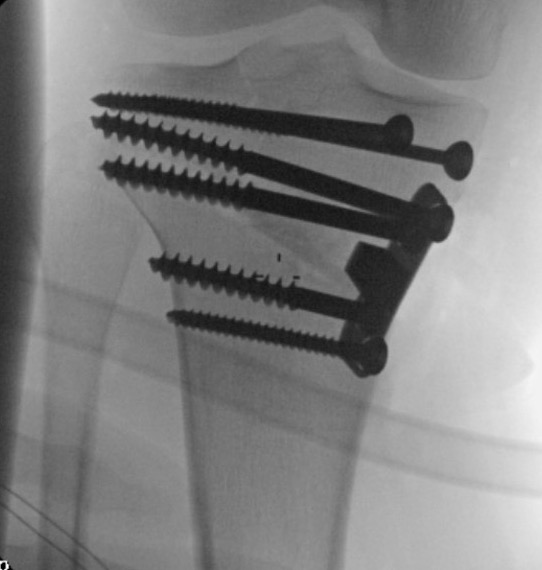

Stabilisation

- locking plates

- +/- autograft / allograft / synthetic bone graft

Arthrex Locking Puddhu plate PDF

Arthrex ContourLock system PDF